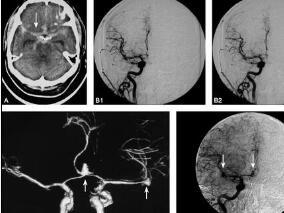

1小时条评论1 病例简介 患者男,51岁,因右上肢麻木,右下肢活动力弱2个月于2009年7月17日就诊于我院门诊。患者2个月前无明显诱因出现右上肢麻木,伴右侧面部发热感,自觉右下肢活动力弱,但不影响行走。左侧肢体均无感觉及活动异常。 既往史:高血压病史10余年,血压最高200...

1小时条评论1 病例简介 患者男,74岁,因头晕、右侧肢体力弱4日于2011年4月26日入院。患者入院前半个月无明显诱因反复出现头晕(呈昏沉感),无视物旋转,站立或坐位头晕明显,平躺后减轻,与转颈和动作姿势无关,每次头晕发作持续1~2小时。头晕时伴视物模糊,视物时先出现闪...